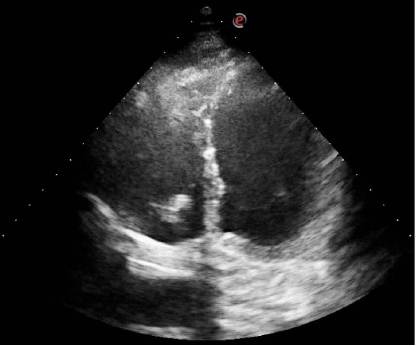

Fig. 1

Ecocardiograma transtorácico, vista apical de 4 cámaras. Se aprecia en ventrículo derecho imagen compatible con vegetación de válvula tricúspide.